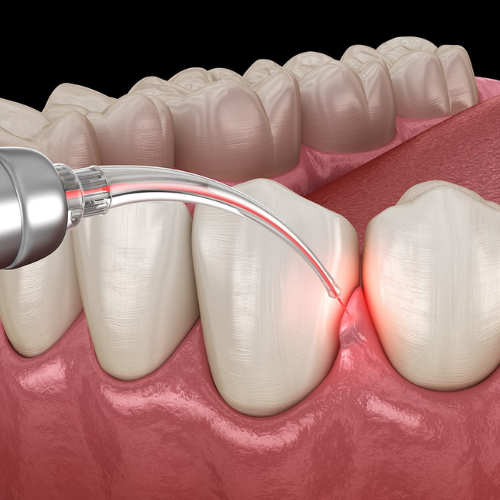

Scaling / Oral Checkup

Deep cleaning and routine oral health check.